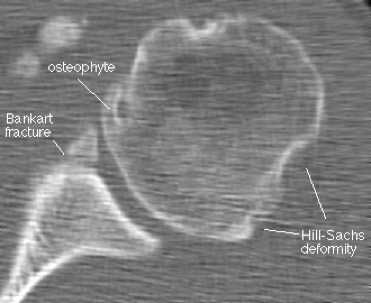

КТ при нестабильности плеча

А - дисплазия гленоида;

В - повреждение Хилл-Сакса (субхондральный перелом), дефект головки плечевой кости после вывиха плеча;

С - повреждение Банкарта (отрыв ободка от костной впадины с вывихом плеча вперед, разрушение краев лопаточной впадины - места прикрепления хряща);

D - повреждение Хилл - Сакса в переднем отделе суставной губы;

Е - 3D-реконструкция переднего вывиха плеча;

F- задний перелом с вывихом плеча.

Наиболее часто КТ плечевого сустава выполняют по поводу травматических повреждений. Они различаются по механизму альтерации: падение на вытянутую руку, прямой удар и пр. Врач-рентгенолог после анализа томограмм выявляет причину, а ортопед определяет оптимальную тактику ведения. Иногда повреждение может быть настолько серьезным, что пациенту необходимо эндопротезирование плечевого сустава.

- Повреждение Хилла-Сакса: передний вывих с дефектом кости на заднелатеральной поверхности головки плечевой кости; соответствует месту, где головка плечевой кости находит на нижнюю границу суставной полости; возможно изображение в прямой проекции с пронацией плеча.

- Реверсный дефект Хилла - Сакса: возникает при заднем вывихе плечевого сустава; рядом с поврежденным бугорком плечевой кости.

- Повреждение Банкарта: дефект хрящевой ткани и/или кости на нижней границе

суставной полости/суставной губы.

Наиболее типичным (около 85% передних смещений травматической этиологии) является повреждение Банкарта - отрыв фиброзного или фибрознохрящевого фрагмента от края суставной впадины в месте прикрепления связки к суставной впадине с повреждением суставной губы. Кроме того, травма может приводить и к костным повреждениям - перелому гленоидного кольца спереди, костному повреждению Банкарта (то есть повреждению Банкарта в сочетании с переломом) и перелому большой бугристости.

На КТ хорошо видны костные дефекты и дефекты гиалинового хряща суставной впадины. Гиалиновый хрящ, покрывающий головку плечевой кости виден гораздо хуже.

КТ плечевого сустава, Переломы Банкарта и Хилла-Сакса.